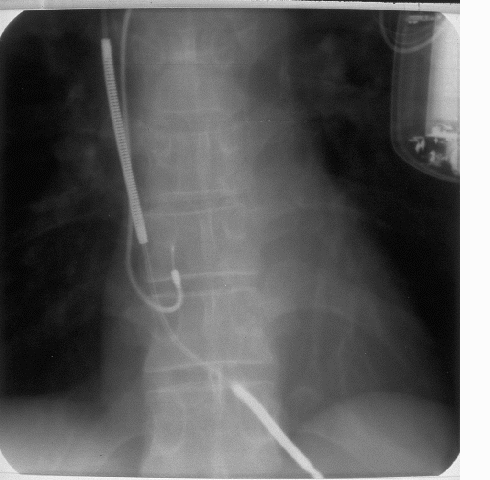

Nång lßþng cn thit ð phá CÐN tùy theo v trí các ði®n cñc sc. Trong trßng hþp Hình 5, có hai ði®n cñc sc ðßþc dùng: nhî phäi (ðúng hn là tînh mÕch chü trên), tînh mÕch vành. Hình 5 là hình quang tuyn các ði®n cñc sc.

Hình 5. Ði®n cñc sc nhî phäi và tînh mÕch vành

Tuy nhiên, v trí ði®n cñc sc tînh mÕch vành chï là tÕm thi. V trí các ði®n cñc khi cy máy xong là nhß trong Hình 6.

Hình 6. V trí ði®n cñc sau ca cy máy.

Trong Hình 6, các ði®n cñc nhß sau: